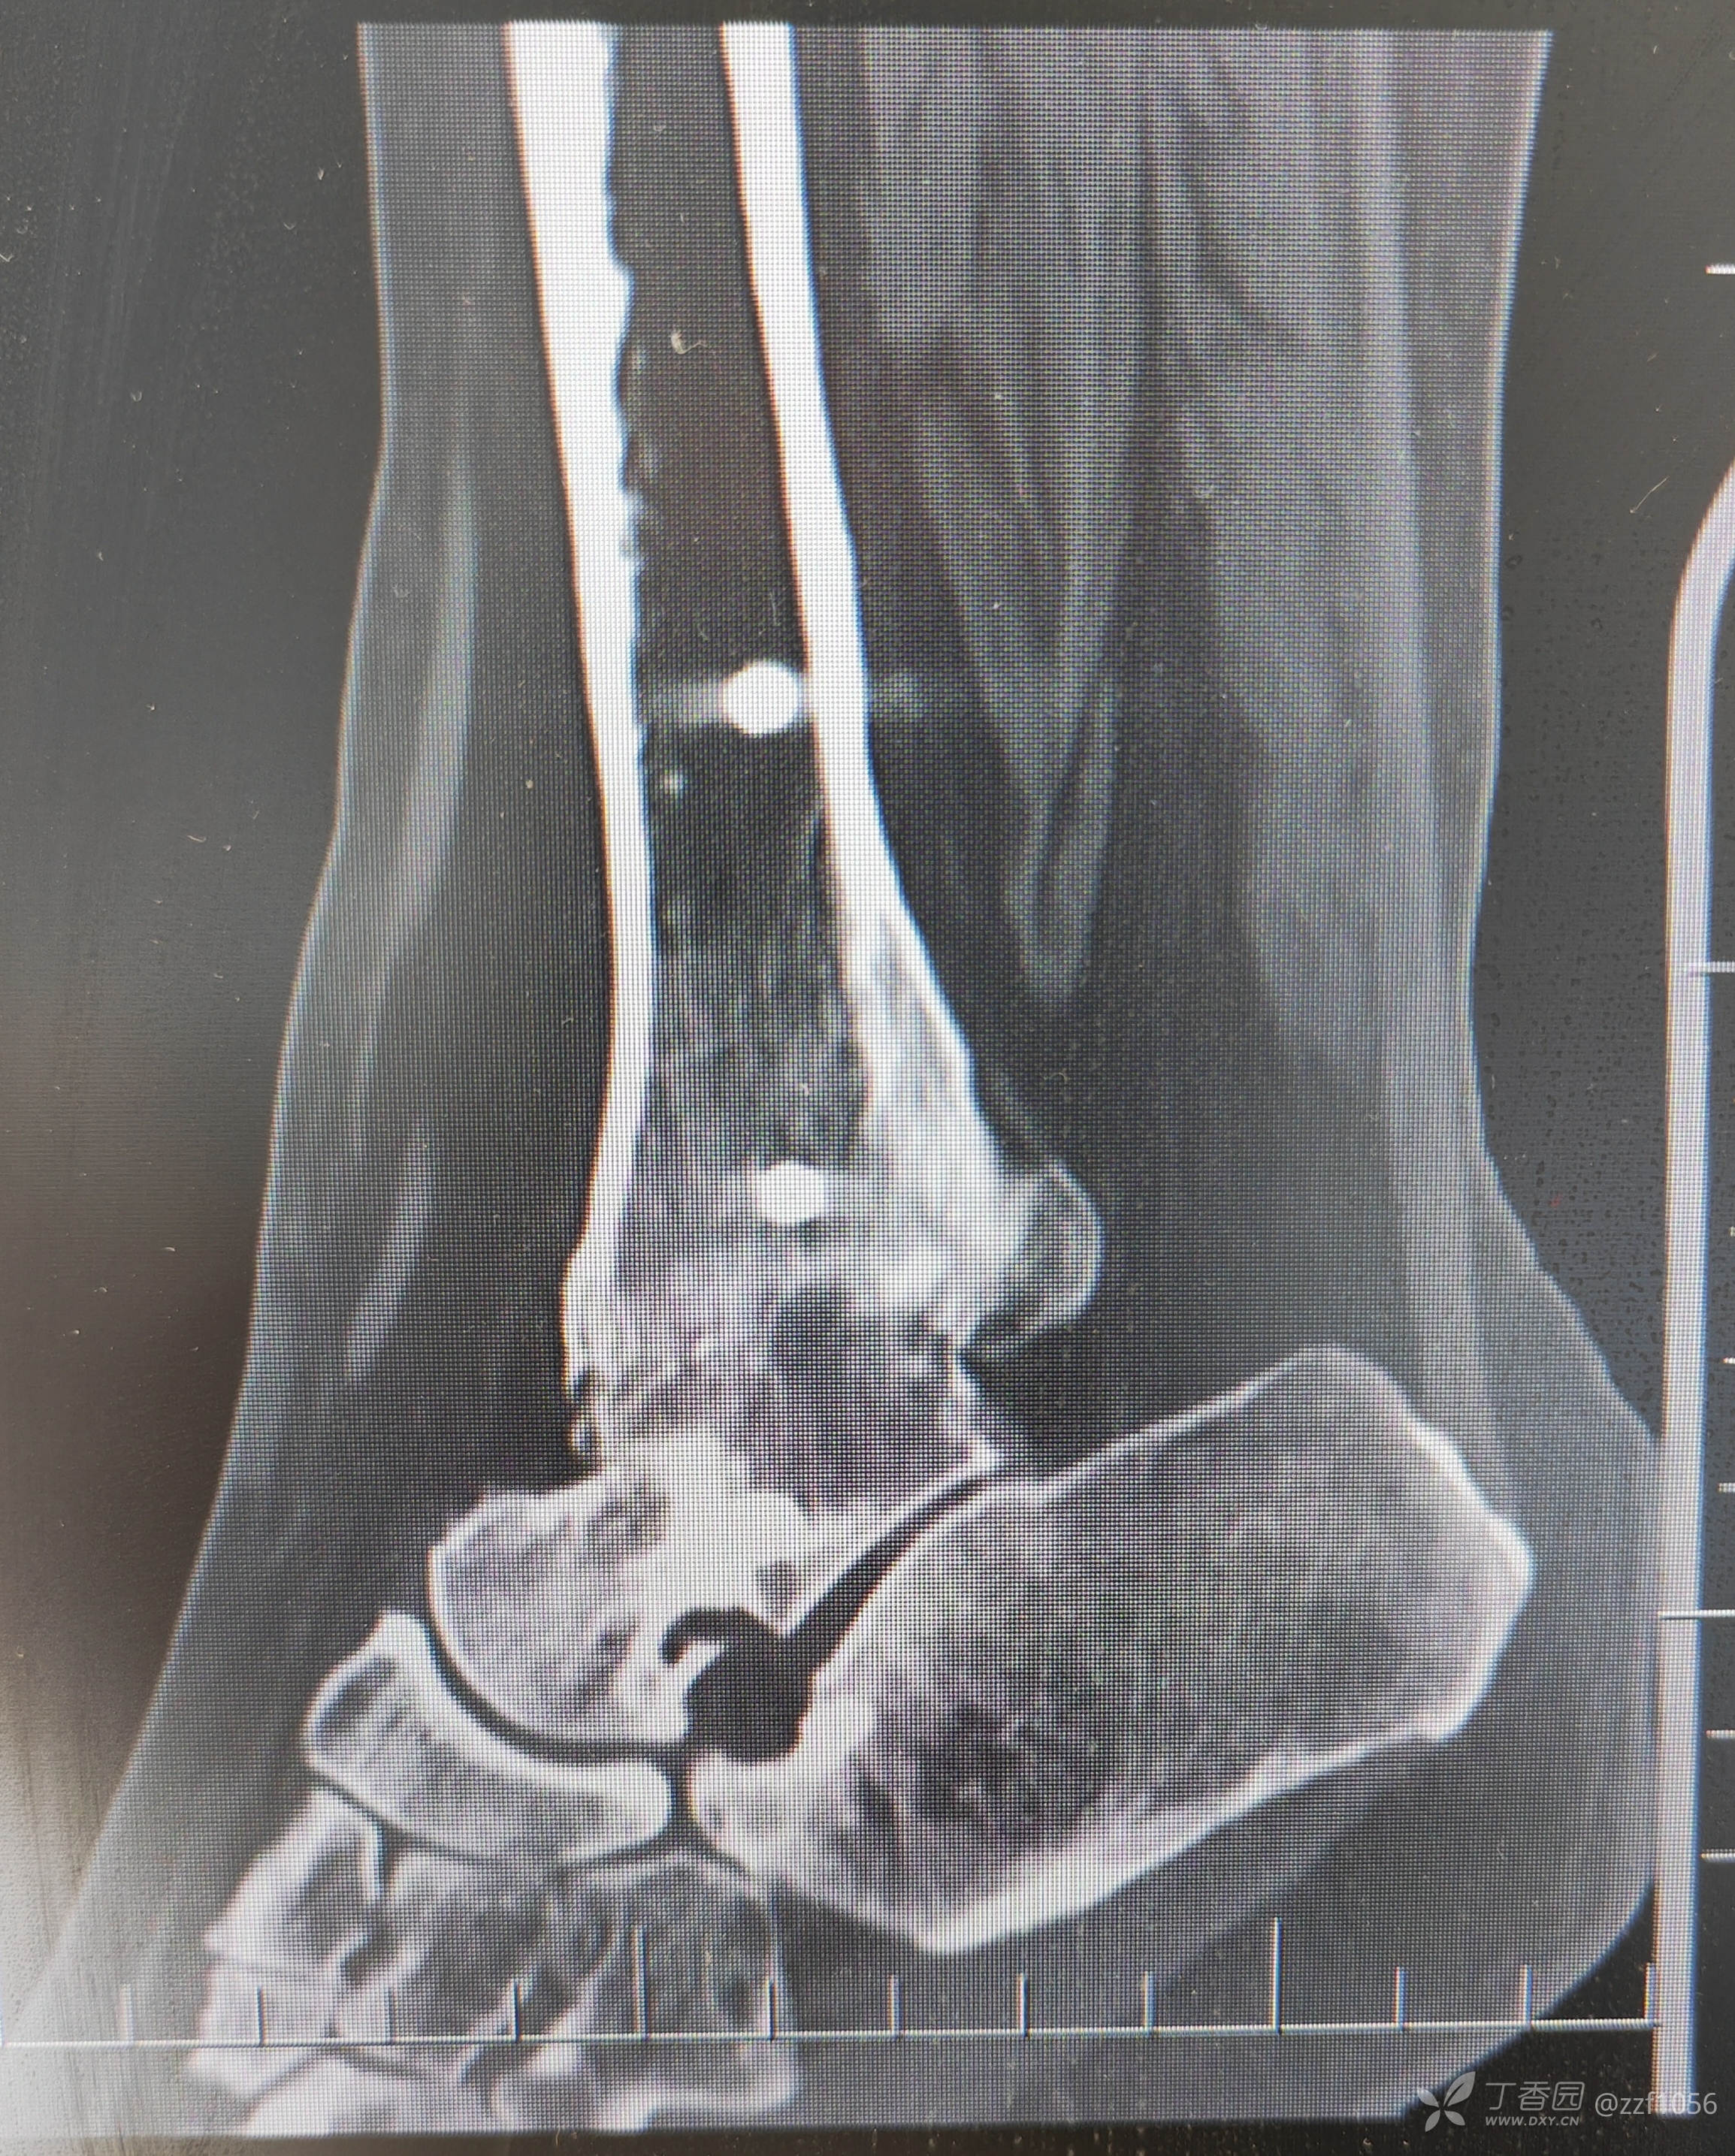

看一下目前CT

从骨折畸形愈合形态应该能推测当时接近于劈木机损伤,旋前外旋四度骨折。

正位片力线